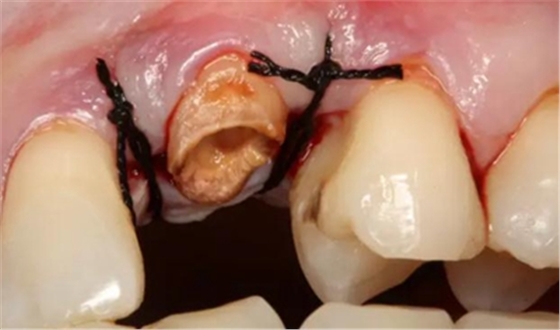

患牙遠(yuǎn)中邊緣嵴完整,強度沒有降低,故擬保留遠(yuǎn)中邊緣嵴,高嵌體修復(fù)。首先去除腐質(zhì)及原墊底材料,流體樹脂+3M Z350XT樹脂墊底。局麻下行冠延長手術(shù)。在此需要提及個人的一個觀點。冠延長手術(shù)原則上要求3-6個月以上才能永久修復(fù)。但是個人喜歡后牙肩臺建立在齦上,所以修復(fù)后的修復(fù)體邊緣位于牙齦上方1mm,對牙周的愈合影響較小(如果為齦下邊緣則要慎重),故該患者術(shù)中按照齦上邊緣的設(shè)計進行冠延長手術(shù)。以下為術(shù)中:

改良垂直褥式縫合關(guān)閉傷口,傷口無明顯滲血,高嵌體預(yù)備完畢后,硅橡膠取模,見邊緣清晰。灌注模型,模型上3MZ350XT分層堆塑高嵌體。